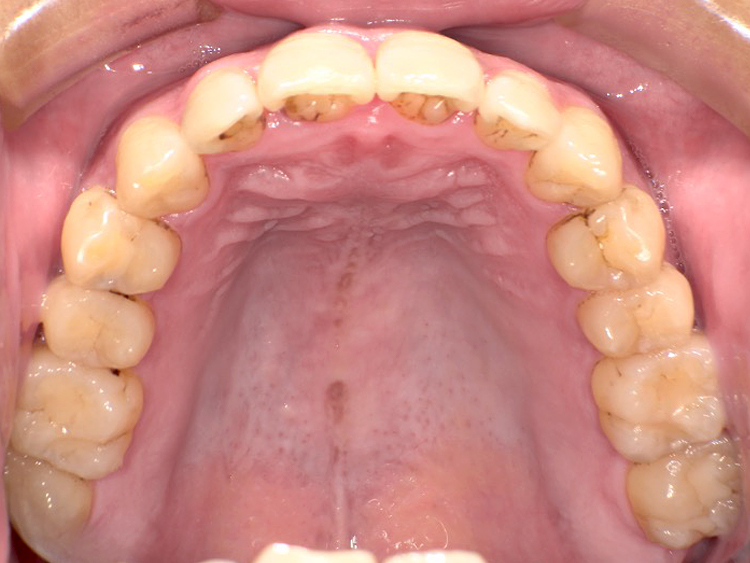

症例3

Before

After

| 主訴 | 上下の歯のガタガタを治したい |

|---|---|

| 年齢 | --- |

| 治療 期間 |

約10ヶ月 |

| 治療 内容 |

インビザラインiGoで上下顎の治療。 狭まっていた歯並びを広げることで、 ガタガタに並んでいた歯を綺麗に並べた。 |

| 治療費 | ¥517,000(税込)+月額調整料 |

| 治療のリスク | 歯と歯の間を削ることでスペースを確保するので、 場合によっては歯が染みる症状が出ることがある。 |